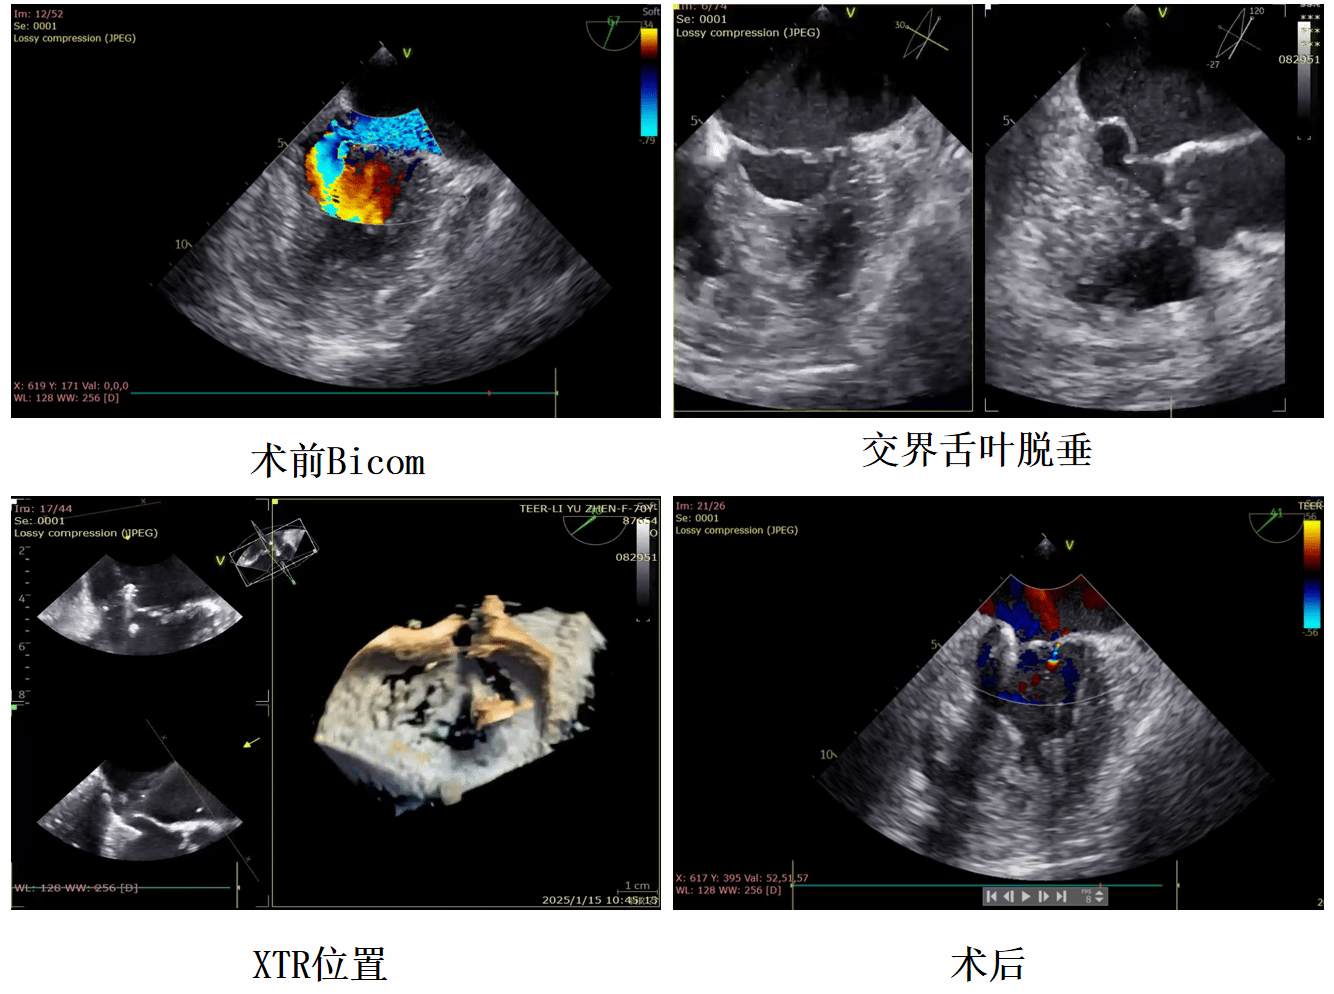

几天前,邓捷主任团队再次成功为一名二尖瓣脱垂患者实施 TEER 手术。患者李阿姨因“胸闷气短10余天”入院,此前因“胆囊结石伴胆囊炎、急性胰腺炎、宫颈癌术后化疗” 在住院治疗期间出现胸闷、气短症状,完善心脏彩超后发现存在二尖瓣 A3 累及内交界脱垂,二尖瓣反流(大量),左房、左室增大,肺动脉增宽,三尖瓣反流(中量)等多种心脏问题。经过详细的超声影像评估,显示可用穿刺高度约 4.1cm,2 区AML长约20mm,PML 长约13mm,瓣口面积5.5cm²,脱垂宽度15mm,高度9mm,患者符合进行 MitraClip手术的指征。鉴于该患者二尖瓣反流情况极其严重,瓣叶脱垂的形态和位置相对复杂。经多学科讨论分析,XTR下在脱垂及返流处可能会有残余脱及返流,放在内侧尽量靠内,改善对合,舌叶被压在前后叶下,有可能空间不够,主要考虑返流3区靠近交界放置一枚XTR,解决脱垂及返流问题,再通过观察到的返流及跨瓣压差进行补充,根据实际情况在外侧补 XTR 以解决反流。

这场手术堪称一场在心脏 “迷宫” 中的极致精细冒险。二尖瓣区域空间狭小,却如同一个精密无比的机械枢纽,任何细微触碰都可能引发 “多米诺骨牌” 效应,导致瓣膜周边结构损伤、大出血、恶性心律失常,或造成其他器官功能障碍。就像在布满荆棘的狭窄小径上小心翼翼地前行,正如术前评估,在李阿姨手术XTR到位过程中由于舌叶被压空间不足,XTR难以通过瓣叶,患者出现室性心动过速,血流动力学出现不稳定,如稍有不慎便会使手术陷入绝境。在这个关键时刻,邓捷主任及团队凭借精湛技术和沉稳操作,最终顺利通过并精准到位成功完成手术。患者术后恢复良好,病情得到有效控制。